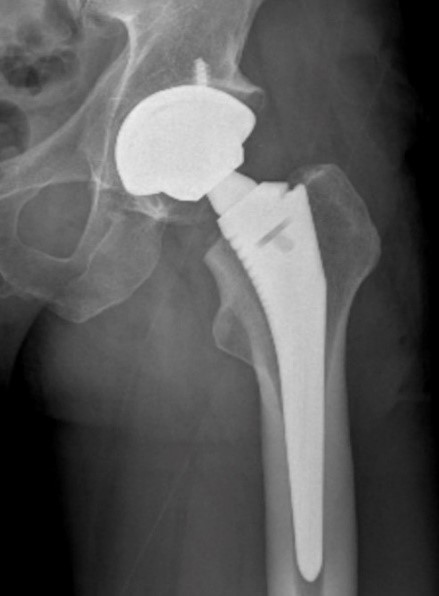

Thay khớp háng nhân tạo là phẫu thuật thay thế xương vùng khớp háng bị hỏng bằng khớp nhân tạo, đây là một tiến bộ lớn của ngành chấn thương chỉnh hình giúp người bệnh cải thiện khả năng đi lại, sinh hoạt và lao động hàng ngày.

Thay khớp háng nhân tạo bằng kỹ thuật Superpath là phẫu thuật mới với đường mổ nhỏ, xâm lấn phần mềm tối thiểu (không cắt khối cơ chậu hông mấu chuyển) nên bệnh đỡ đau, giảm mất máu, phục hồi chức năng thuận lợi nên bệnh nhân sớm trở lại với cuộc sống hàng ngày.

– Cấu trúc khớp nhân tạo với lớp phủ nhám và hình ảnh ở bề mặt chuôi và ổ cối nhân tạo dẫn tới hình thành liên kết vững chắc giữa xương và khớp nhân tạo, làm tăng độ bền và tuổi thọ của khớp. Bên cạnh đó cấu trúc khớp với cổ chuôi dạng module với chiều dài, góc nghiêng và ngả trước khác nhau giúp đảm bảo chiều dài chi, góc cổ thân và hạn chế tỷ lệ trật khớp háng nhân tạo.